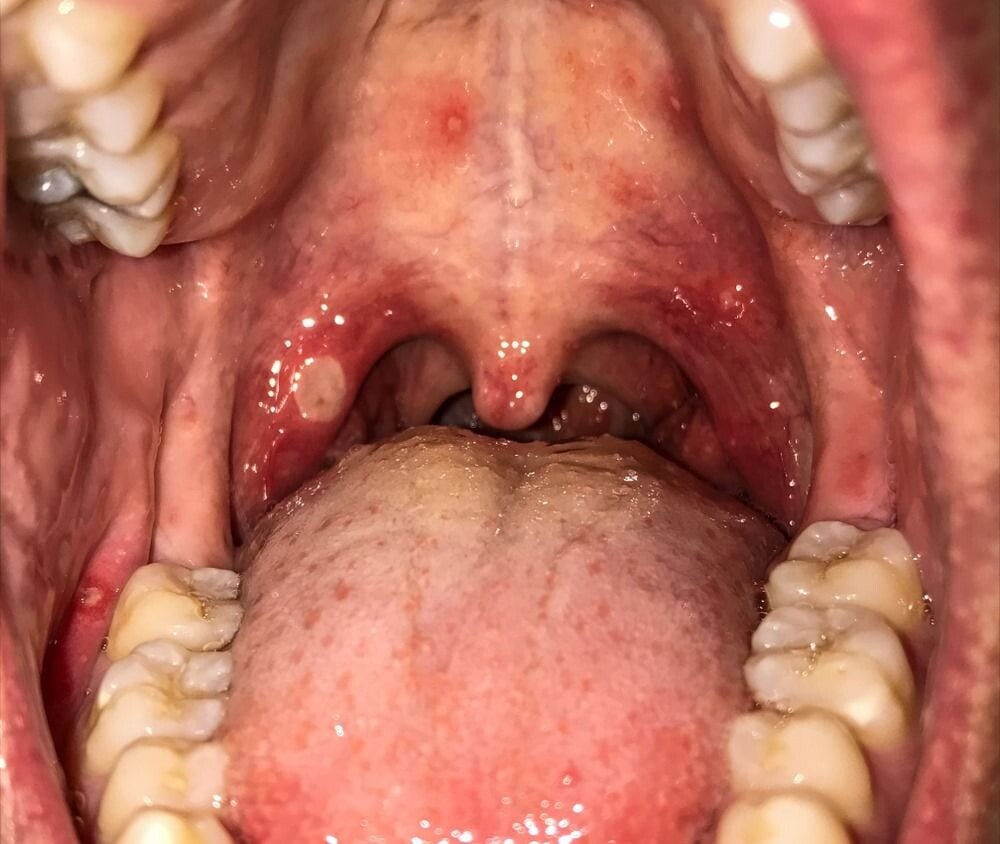

Four Possible Causes of Roof of Mouth Pain & Their Treatments

Why is the Roof of my Mouth Sore?

If the roof of your mouth (palate) is sore, it can make eating and drinking uncomfortable and difficult. You may also have problems speaking normally.

Several things can cause a sore palate, including very hot coffee, infections, allergies, and injuries. In most cases, it's not a serious condition and typically goes away by itself. However, if the pain is severe or lasts more than a few days, contact a medical professional.

Symptoms

The symptoms of a sore palate vary depending on the cause. You might experience:

Pain

Burning or tingling sensation

Difficulty eating or drinking

Bad breath

Swelling

Redness

Visible sores

4 Possible Causes of Roof of Mouth Pain

Here are four potential causes of palate pain:

1. Burns

The roof of your mouth is a delicate and sensitive area that can burn easily. Eating or drinking something too hot can cause a burn.

Burn pain is usually immediate and can be severe. It typically goes away within 3 to 7 days without treatment and commonly heals by itself.1

2. Canker Sores (Aphthous Ulcers)

Canker sores are small, painful ulcers that can develop on the hard palate or anywhere on the soft tissues in the mouth. They’re usually white or yellow with a red border and can make eating and drinking uncomfortable.

The lesions may resemble cold sores but don’t occur on the surface of lips and are not contagious.

3. Cold Sores (Fever Blisters)

The herpes simplex virus causes cold sores. If the roof of your mouth hurts and you can see blister patches, they could be cold sores. These mouth sores usually appear on the lips but can also develop on the hard palate.

4. Oral Cancer

Although the causes of a sore palate are typically harmless, some, such as oral cancer, are more serious. Mouth cancer causes cells to divide without stopping and spread into surrounding tissues. It can develop on the tongue, gums, palate, or anywhere else in the mouth.

Identifying mouth cancer early is the key to successful treatment. Therefore, if your palate is still sore after 10 days, see your doctor or dentist for an evaluation.5